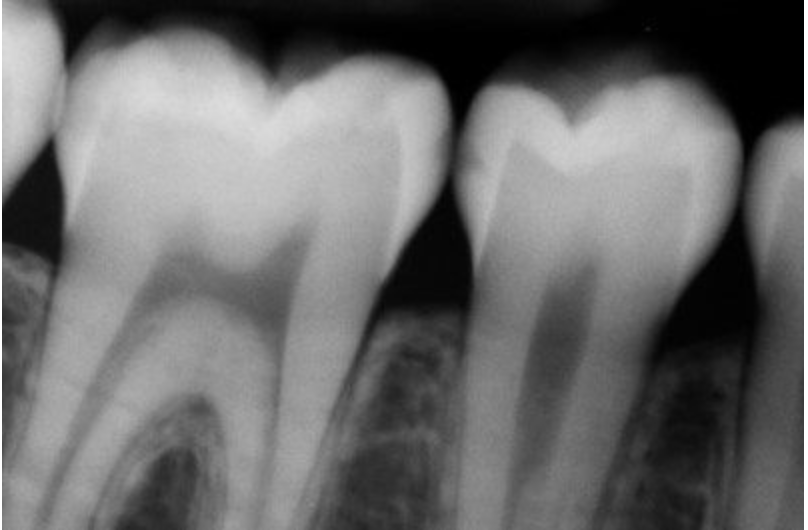

Стоматологические Исследования: Рентген Инвагинации Зубов